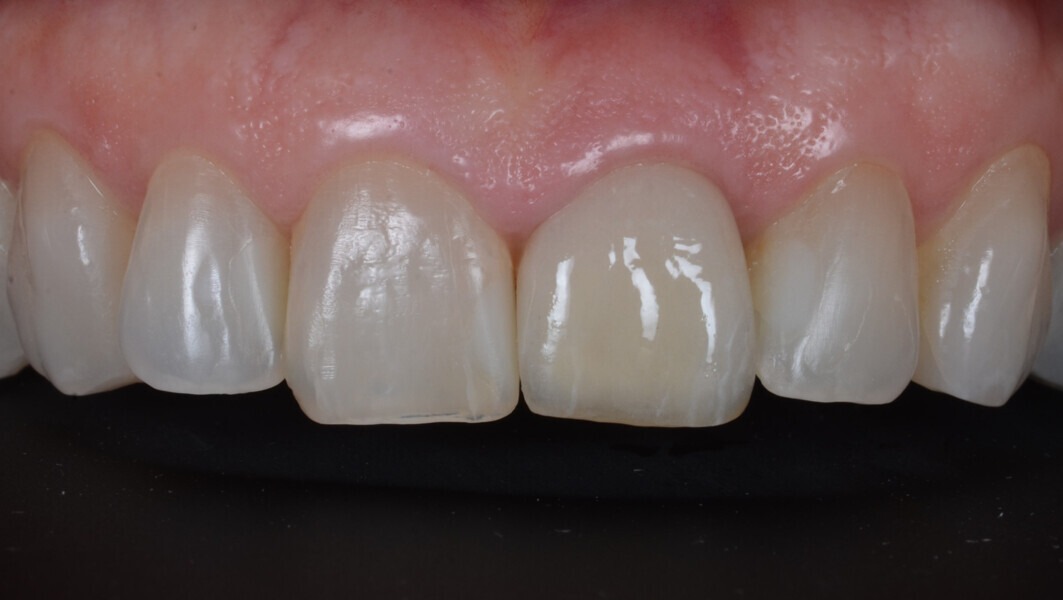

Fig. 32: Final result close up.